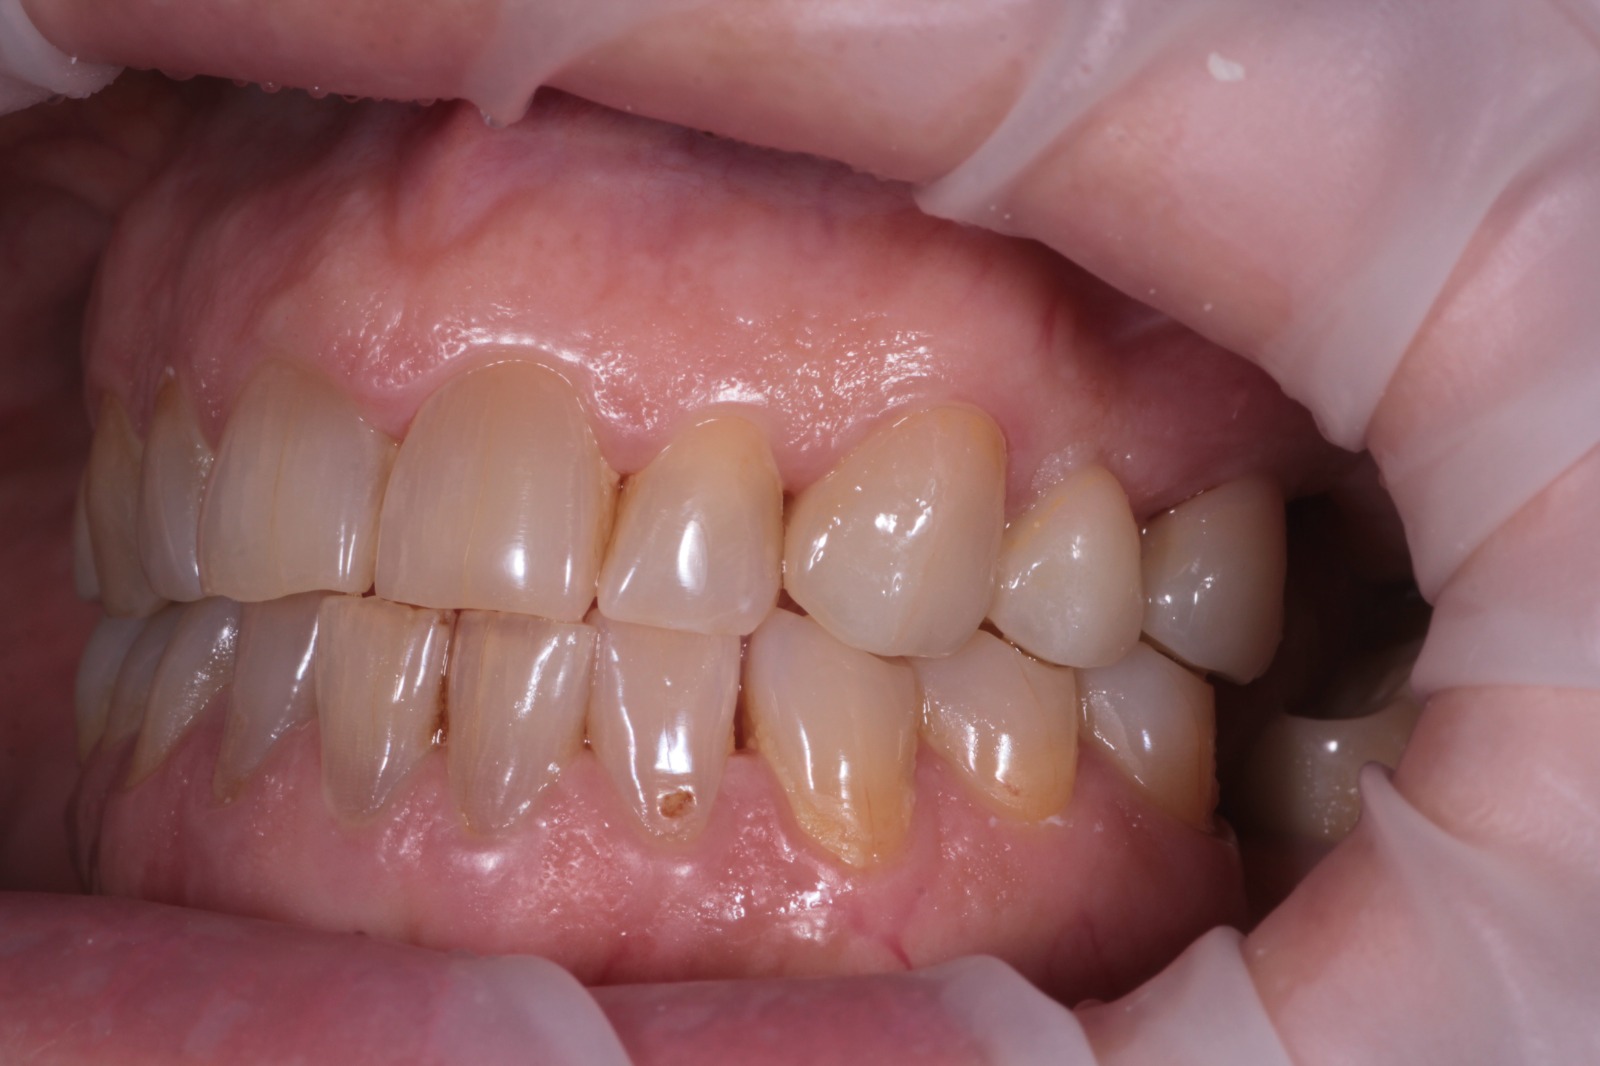

надёжное восстановление жевательных зубов

Коронки из диоксида циркония на жевательные зубы могут выглядеть естественно и натурально. В этой работе цвет и анатомия коронки подобраны так точно, что её сложно отличить от своих зубов

Сможете найти коронку из циркона?